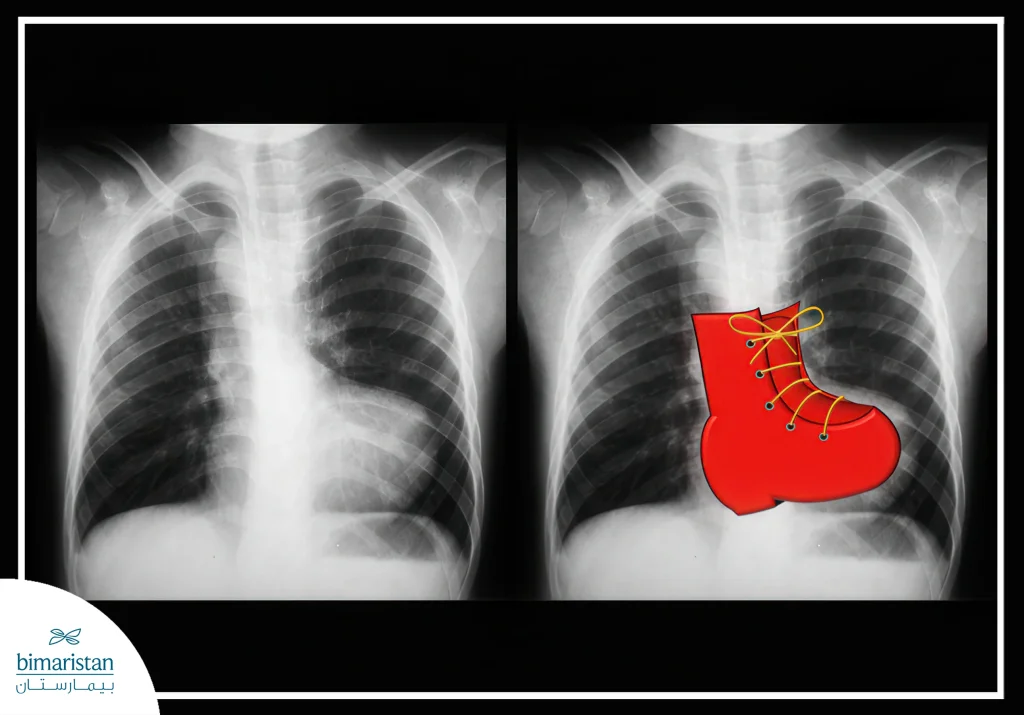

- الأشعة السينية للصدر (Chest X-ray): تُظهر شكل القلب والرئتين، وأحياناً تظهر القلب بشكل يشبه الحذاء بسبب تضخم البطين الأيمن.